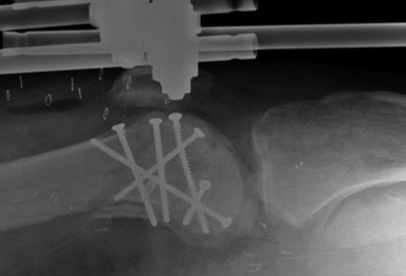

Unicondylar Fixation

1.  AP screws

Hoffa Fracture ORIF APHoffa Fracture Lateral

2.  PA screws

Hoffa Fracture ORIF PA screws

3.  Combined

Hoffa fracture